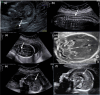

Methods: We used whole-exome sequencing in a consanguineous Turkish family with four siblings presenting with Pierre Robin sequence, arthrogryposis, heart malformation, splenomegaly, hydrocephaly, corpus callosum dysgenesis, brainstem, and cerebellar hypoplasia.

Results: We identified a novel homozygous pathogenic variant in exon 9 of COG6 (NM_020751.2): c.821del, p.(Arg274Lysfs*32). In this family, our post-mortem study led us to describe further the prenatal phenotype of CDG2L. In addition, it permits correlating the most relevant anomalies to a maldevelopmental cascade due to a neurodegenerative process of metabolic origin, affecting the entire central nervous system including the spinal cord.